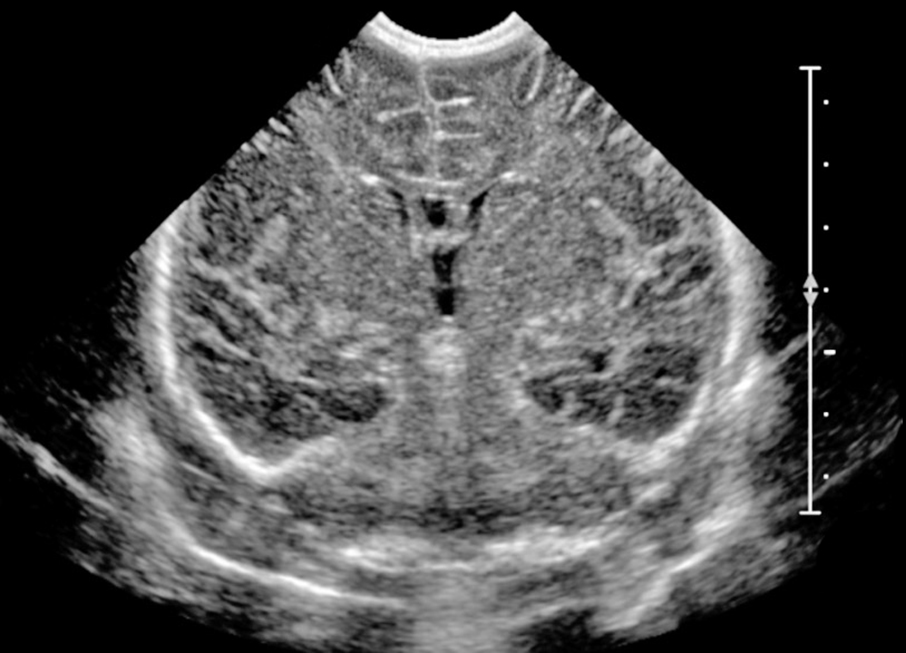

НСГ можно делать вплоть до года, пока открыт большой родничок. После его закрытия, примерно в 12-18 месяцев, стандартный доступ через родничок становится невозможным. Однако существует транскраниальная нейросонография — исследование через височные кости черепа, которые остаются достаточно тонкими для прохождения ультразвука и в более старшем возрасте. Этот метод позволяет оценить состояние желудочковой системы и кровоток, но его информативность ниже: тонкие изменения субарахноидальных пространств он уже не покажет. При необходимости полноценной визуализации после закрытия родничка используется МРТ, которое требует медикаментозной седации у детей раннего возраста.

МРТ в 4 года показало отсутствие структурных патологических изменений: ликвор нормализовался. Но диагноз РАС есть. И это ставит закономерный вопрос: что происходило в период между первой НСГ и чистым МРТ?

Первые два года жизни — период максимального синаптогенеза. Именно тогда мозг закладывает нейронную архитектуру, с которой человек живёт всю жизнь. В норме субарахноидальное пространство увеличивается с рождения до 7 месяцев, затем убывает и к 2 годам становится минимальным. Нейронные сети формируются параллельно, в тех условиях, которые есть.

Что если расширенные ликворные пространства в этот критический период создавали механическое давление на кору именно тогда, когда она выстраивала связи? Мозг не ждёт нормализации. Он прокладывает пути там, где возможно. Не всегда по привычным маршрутам. Возможно, именно поэтому — альтернативный вариант работы мозга. Это не домысел. Это логика, которую наука уже начала проверять.